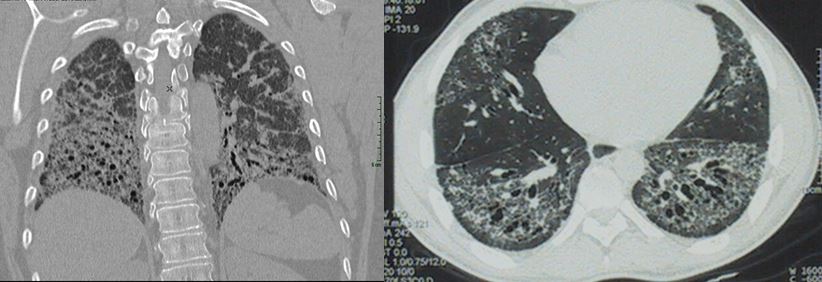

Atteinte pulmonaire interstitielle au cours de la sclérodermie systémique